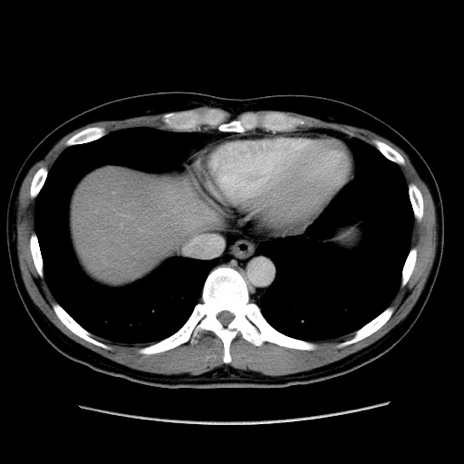

症例4(横断像)

【症例】30歳代男性

【主訴】腹痛、嘔吐

【現病歴】昨晩から突然の腹痛あり、その後嘔吐、軟便も出現。腹痛が改善しないため救急搬送となる。2日前にしめ鯖の食事歴あり。

【身体所見】意識清明、苦悶様、BP 135/90mmHg、BT 35.7℃、腹部:平坦、やや硬、心窩部〜臍部に自発痛、圧痛あり、筋性防御+、反跳痛-

【データ】WBC 8100、CRP 0.57